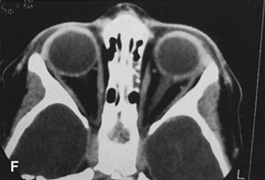

Magnetic resonance imaging is useful in selected cases, especially when evaluating the orbital cranial junction. Significant bony artifact and a lack of orbital fat in the orbital apex make CT scan resolution of the orbital apex structures poor. Because cortical bone has low signal on MRI, there is no bone artifact when viewing the orbital apex on MRI. The lack of intervening fat in the apex to provide contrast is overcome on MRI because contrast is provided by the individual nuclear characteristics of each tissue so that the orbital apex structures are visualized well. Consequently, conditions that affect the optic nerve and chiasm, such as optic nerve meningioma and glioma, generally are evaluated with MRI rather than CT scan (Fig. 2).

Fig. 2. A. Axial orbital CT scan of right optic nerve meningioma. Note lack of detail in orbital apex. B. Axial orbital MR image, same patient. Note increased detail in orbital apex owing to lack of bone artifact. C. MRI with gadolinium contrast. Note extension into brain not easily appreciated with CT scanning or MRI without contrast.

Use of a contrast agent such as gadolinium can further enhance the T1 signal intensity of lesions and is particularly helpful in imaging areas where there has been a breakdown in the blood–brain barrier. Because orbital fat produces a bright signal on T1-weighted images, orbital MR usually is performed with “fat suppression” to prevent masking of lesions. However, incomplete fat suppression can produce artifacts that may be misinterpreted as abnormal enhancement.